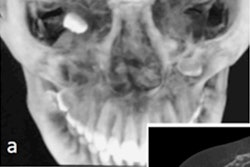

In a March 2 case at Memorial Hermann-TMC, Dr. Martin Citardi used AR technology to perform revision image-guided functional endoscopic sinus surgery for recurrent chronic rhinosinusitis, according to the institution. The patient also had a fibro-osseous lesion blocking drainage from the left frontal sinus.

UTHealth sinus surgeons affiliated with Memorial Hermann-TMC have used augmented reality technology to perform minimally invasive sinus surgery. Image courtesy of Dr. Martin Citardi of UTHealth.The surgeons used Scopis TGS target-guided surgery technology, which allows for surgical planning from preoperative imaging studies. This planning is overlaid onto the surgeon's endoscopic view of the surgical area, assisting the surgeon in following the defined pathway and avoiding critical structures, according to Memorial Hermann-TMC.